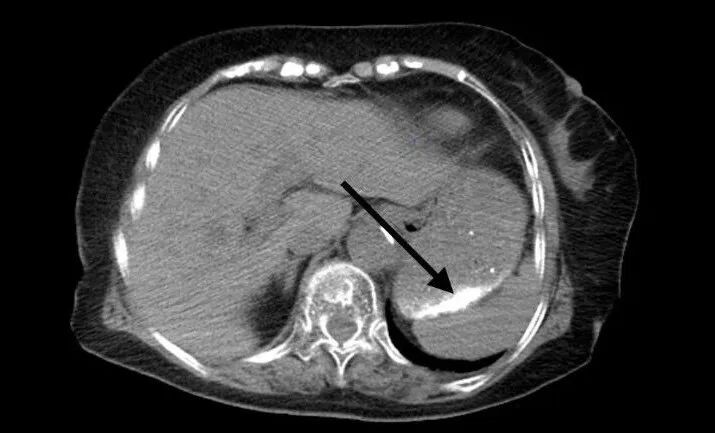

CT结果提示:

胃部及部分小肠内可见多发致密影。这意味着误食的粉末已散布于上消化道,如不及时处理,可能导致化学性灼伤、肠穿孔甚至肠梗阻等严重后果。

CT检查结果